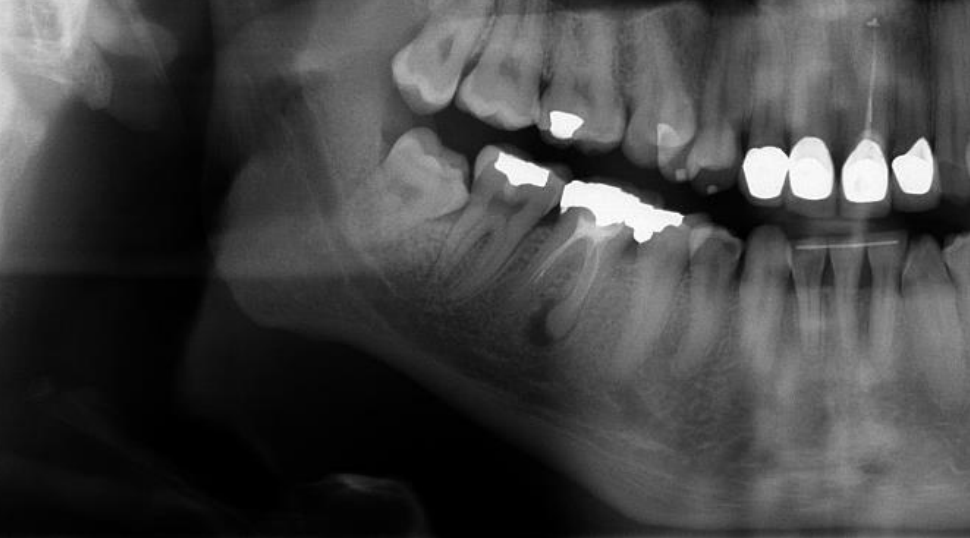

54

What is seen in these radiographs?

Cementoblastoma